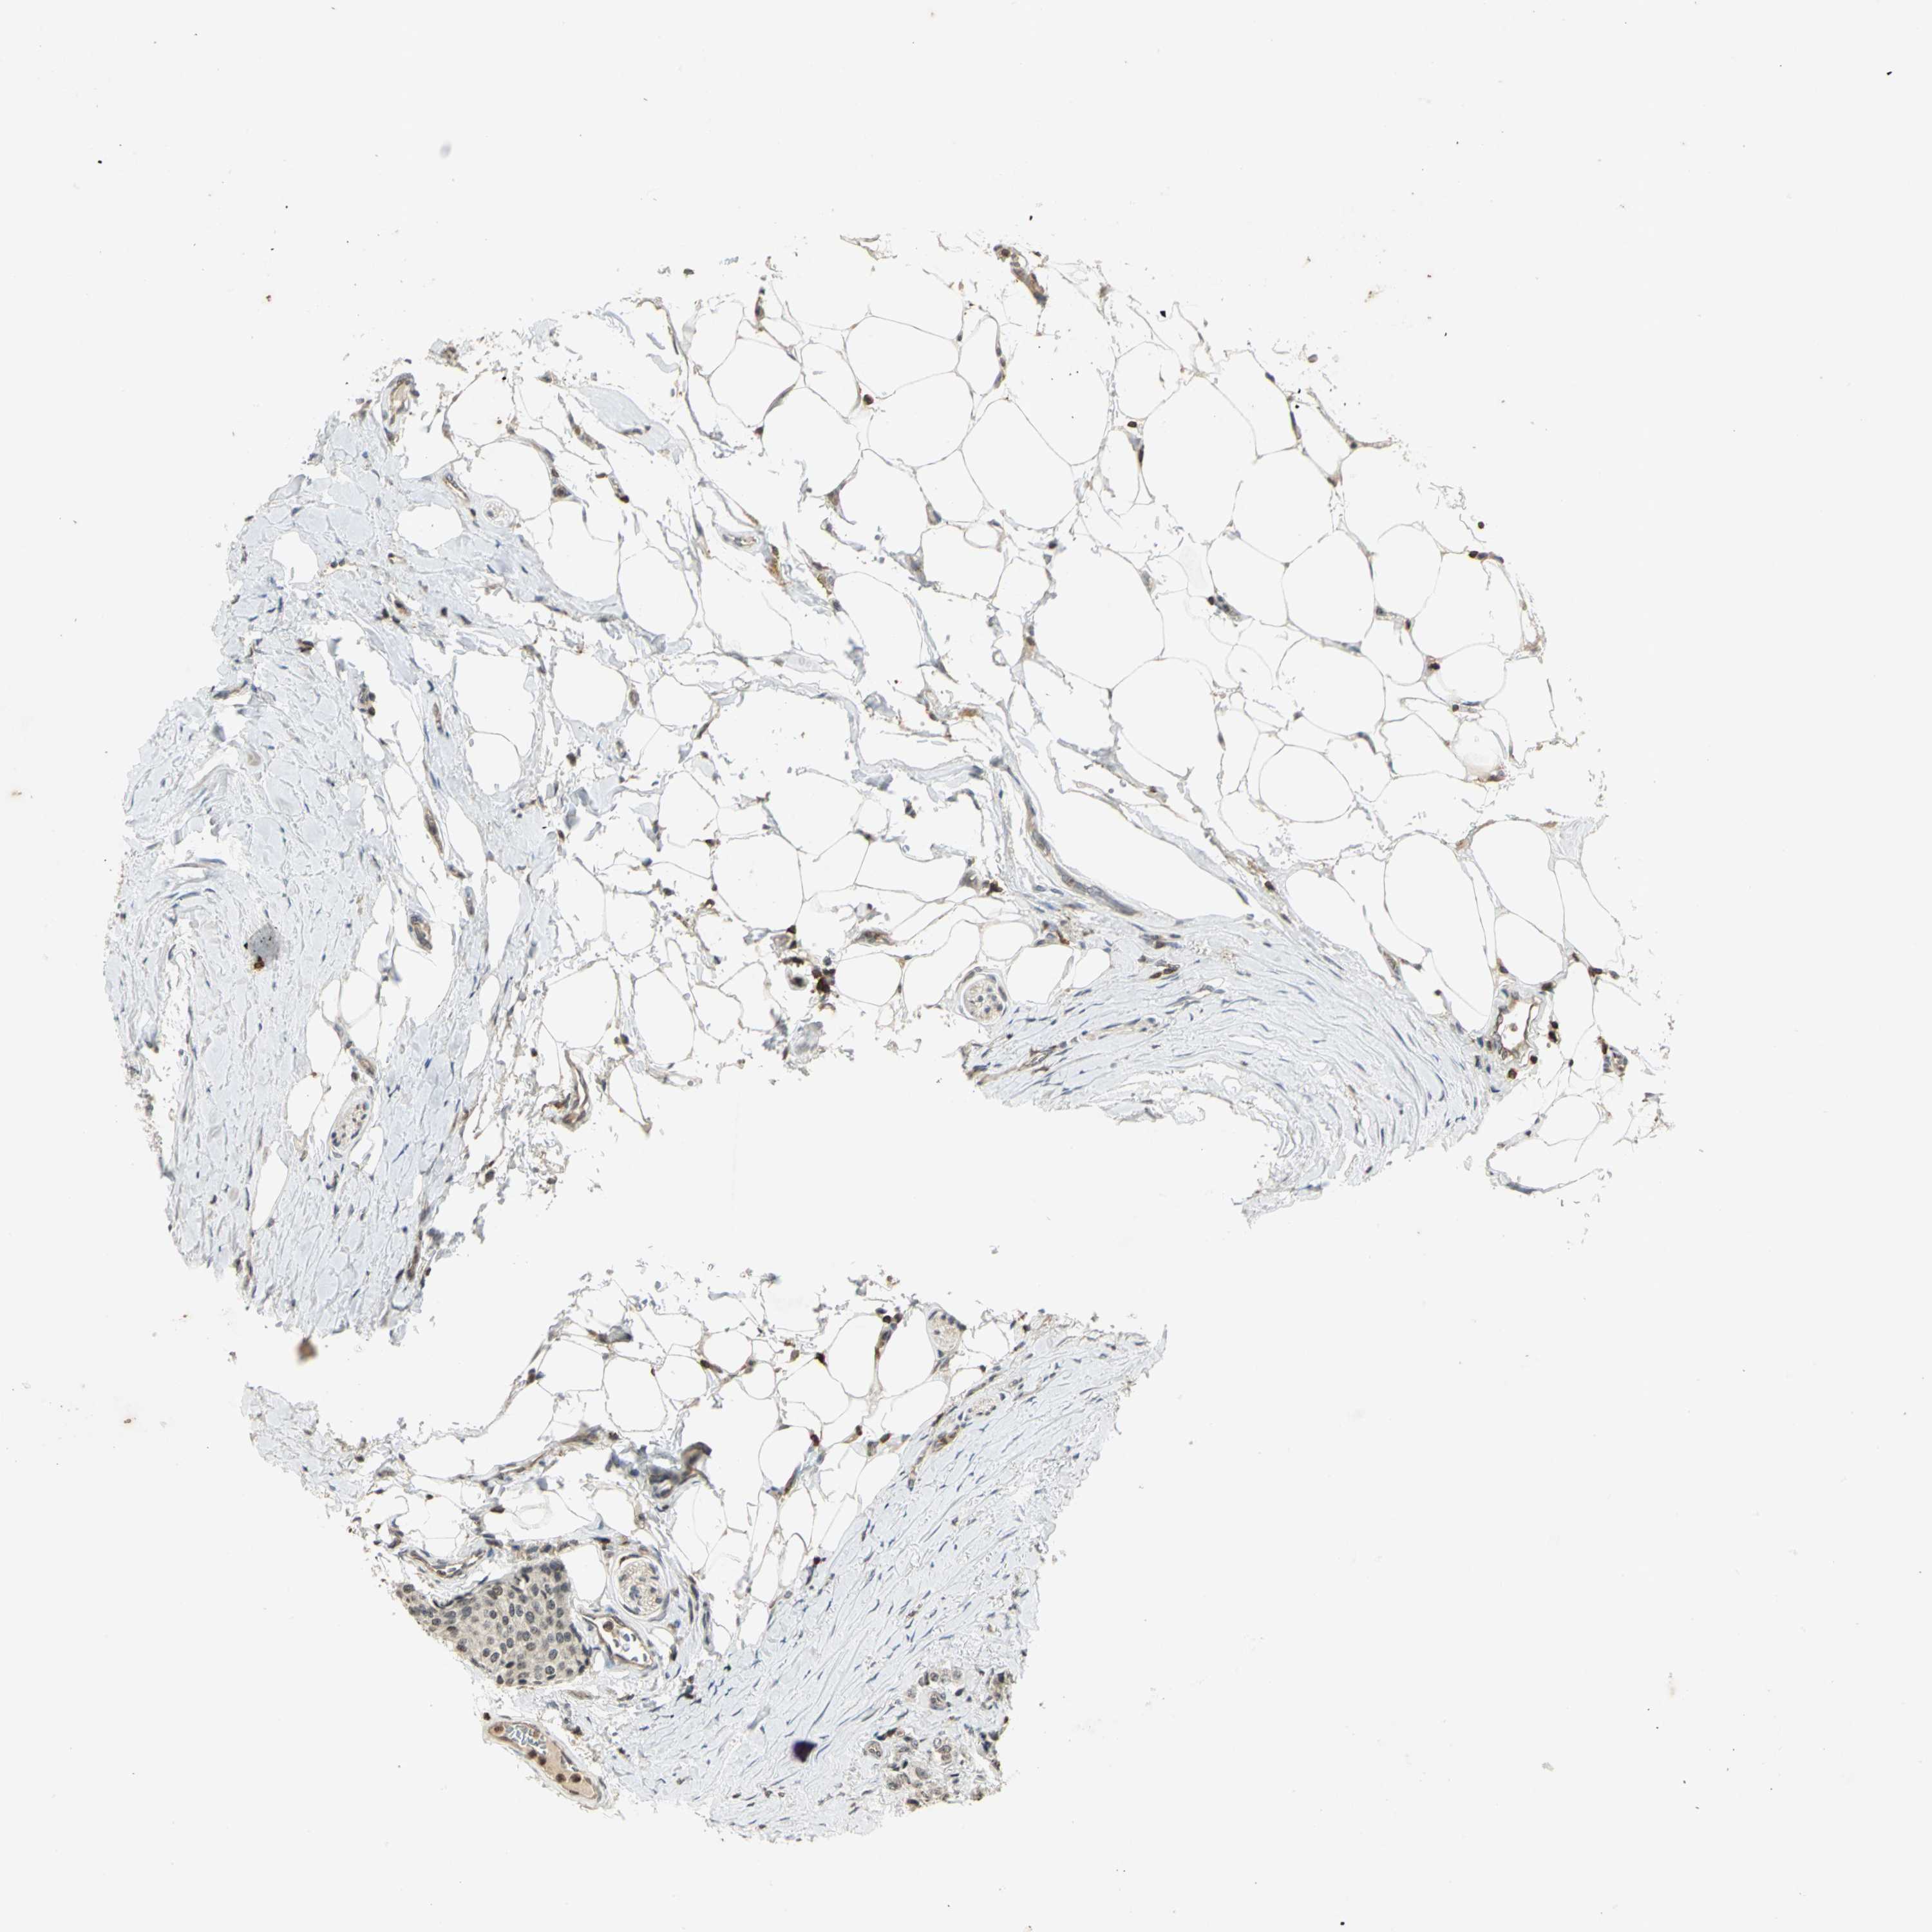

CARCINOID - Protein expressioni

A mouse-over function shows sample information and annotation data. Click on an image to view it in a full screen mode. Samples can be filtered based on level of antibody staining by selecting one or several of the following categories: high, medium, low and not detected. The assay and annotation is described here.

Antibody stainingi

Antibody staining in the annotated cell types in the current human tissue is reported as not detected, low, medium, or high, based on conventional immunohistochemistry profiling in selected tissues. This score is based on the combination of the staining intensity and fraction of stained cells.

Each image is clickable and will lead to virtual microscopy that enables deeper exploration of all samples and also displays staining intensity scores, fraction scores and subcellular localization as well as patient and tissue information for each sample.

Antibody CAB005247

Carcinoma, NOS

Carcinoid, malignant, NOS